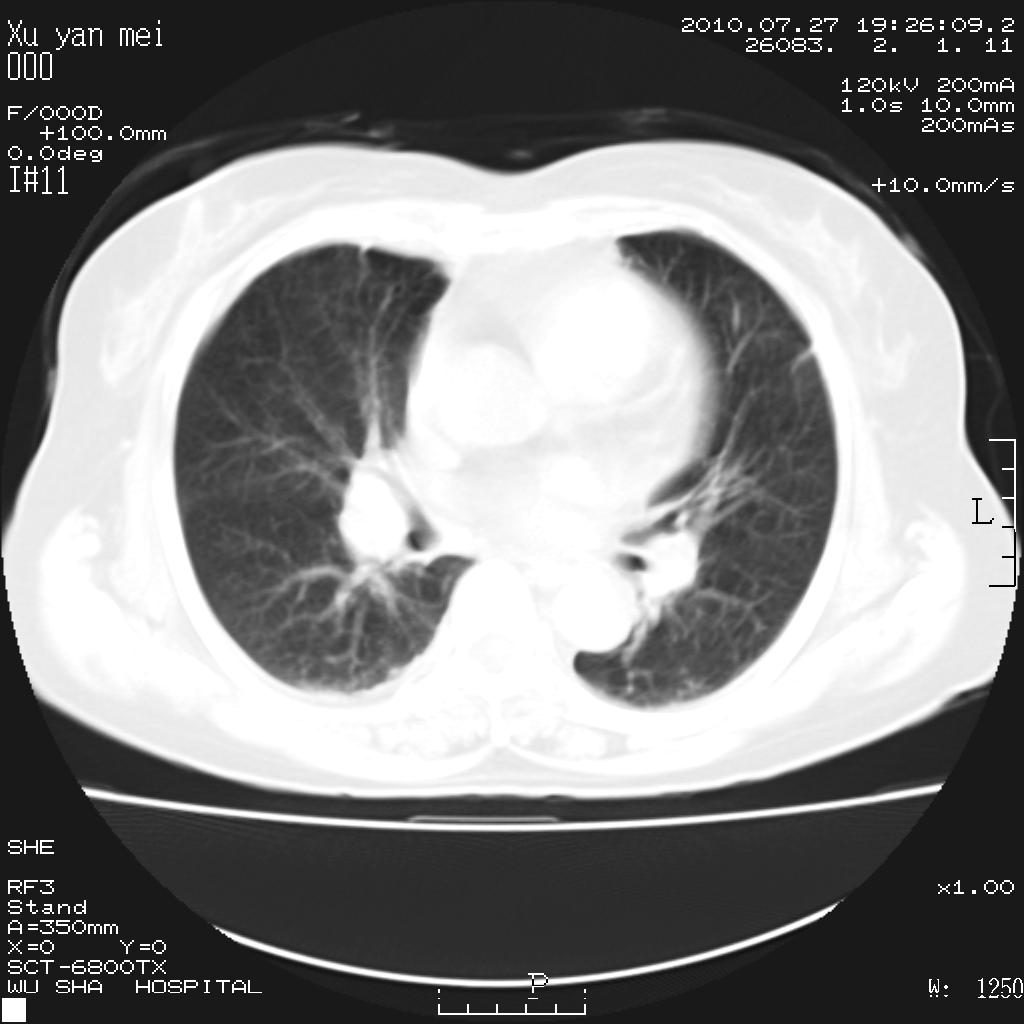

女,60岁,胸痛就诊,右肺结核?炎症?其它?(胸片右侧中上肺野确实看不到什么啊)

1)考虑两肺感染性病变;建议抗炎治疗后复查。2)双侧少量胸腔积液。

1)考虑两肺感染性病变;建议抗炎治疗后复查。2)右侧少量胸腔积液。

右侧少量胸腔积液,段性肺炎。

渗出性 炎性或tb【esr]

双肺炎症可能性大,建议抗炎后复查。右侧胸腔少量积液。双侧胸膜轻度增厚。

考虑两肺感染性病变;不除外肺栓;建议抗炎治疗后复查。